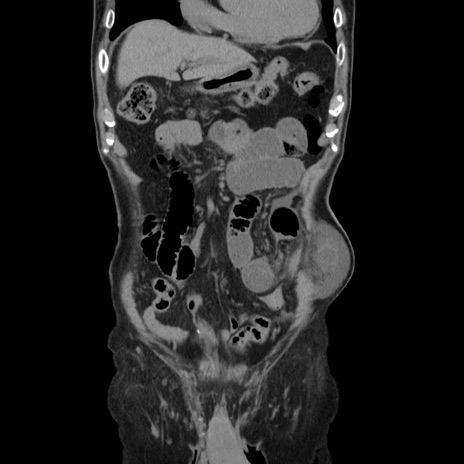

症例24(冠状断像)

【症例】80歳代男性

【主訴】左側腹部痛、嘔吐

【現病歴】本日早朝より左腹部に痛みあり。昼頃嘔吐認めたため、救急要請。

【既往歴】直腸癌(Mile手術)、胆摘

【身体所見】意識清明、BT 35.9℃、BP 221/93mmHg、SpO2 97%(RA) 、腹部:左ストーマ周囲に限局性の腹部膨隆あり。 膨隆部自発痛・圧痛あり・軟。

【データ】WBC 7700、CRP 0.09